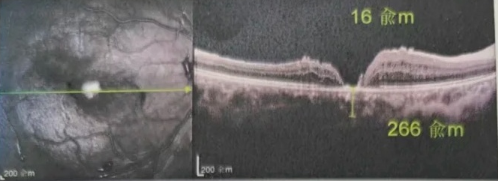

去年年底,年逾7旬的吳爺爺突然發(fā)現(xiàn)右眼看不清,且看東西變形,到當(dāng)?shù)蒯t(yī)院檢查后確診黃斑裂孔。此后他輾轉(zhuǎn)求醫(yī),經(jīng)歷了兩次玻切聯(lián)合內(nèi)界膜剝除術(shù),每次術(shù)后都嚴(yán)格“趴睡”一個(gè)月。然而結(jié)果令人失望:裂孔不但沒(méi)閉合,反而持續(xù)擴(kuò)大,甚至還并發(fā)高眼壓。

由于自身患有頸椎病,每次術(shù)后長(zhǎng)期的趴睡都讓他痛苦不堪。為了尋求更好的治療,吳爺爺來(lái)到廈門(mén)大學(xué)附屬?gòu)B門(mén)眼科中心,找到了眼外傷及眼底病2科的李海波博士后。此時(shí),吳爺爺右眼的黃斑裂孔已經(jīng)持續(xù)擴(kuò)大到780μm,演變?yōu)殡y治性的大裂孔。

最讓吳爺爺難以置信的是:術(shù)后只需保持平躺24小時(shí)!第二天復(fù)查時(shí),眼底鏡及OCT檢查清晰顯示——那個(gè)折磨了他大半年的大裂孔,竟然閉合了!且吳爺爺?shù)挠已垡暳τ辛嗣黠@的改善,術(shù)后3天已經(jīng)可以看到 0.15。